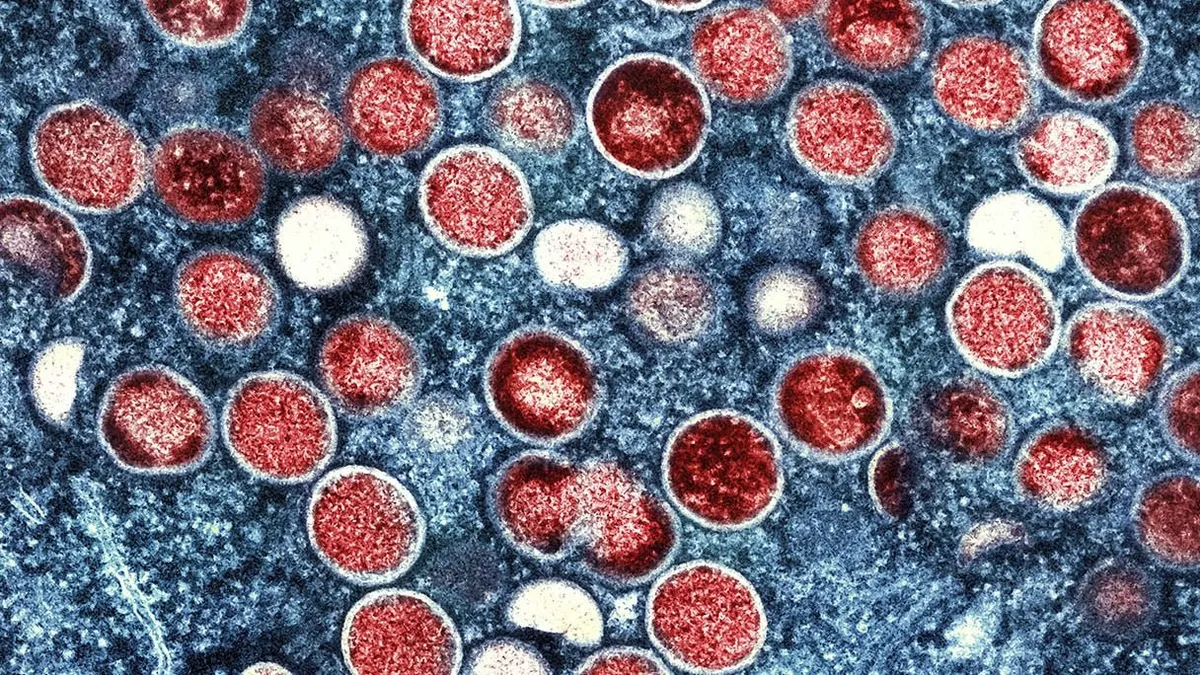

Veszélyes himlővariáns jelent meg – 5-10 százalékos halálozási aránnyal

A Kongói Demokratikus Köztársaság (KDK) kutatói figyelmeztetnek: az Mpox (Majomhimlő) vírus egy új, veszélyes törzse nemzetközi terjedés előtt állhat. Ez a változat súlyosabb tüneteket és magasabb halálozási arányt mutathat, mint korábbi társai - közölte a Sky News .